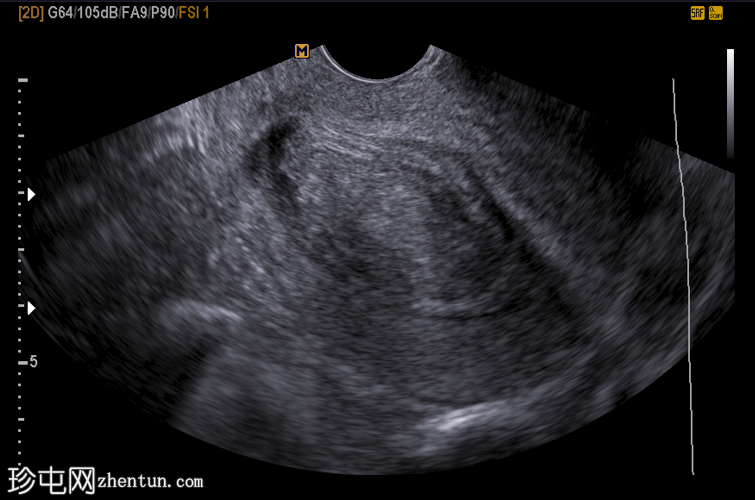

纵切面

经阴道超声显示:

子宫内膜内可见边界清晰的卵圆形宫腔内病变

回声均匀,较子宫肌层高回声

周围有子宫内膜积液

主要鉴别诊断为黏膜下肌瘤。子宫内膜息肉通常为边界清晰、回声均匀的宫腔内病变,起源于子宫内膜;而黏膜下肌瘤起源于子宫肌层,通常回声不均匀,并可能出现后方声影。